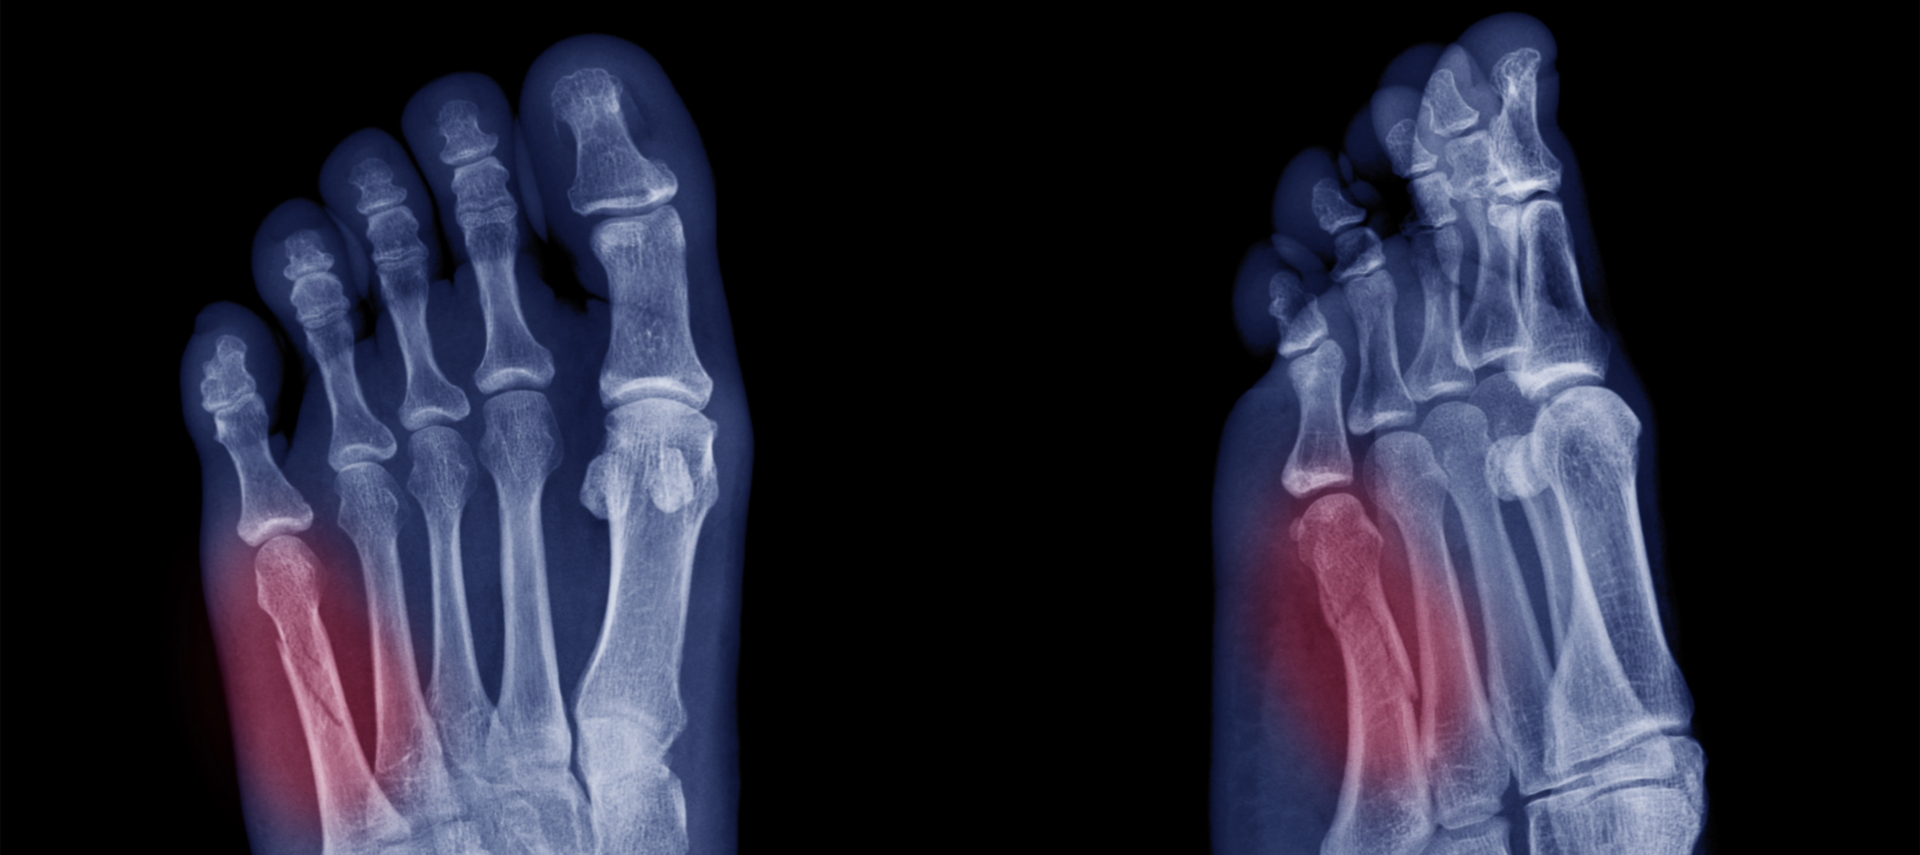

골절

골절 이란?

외상(넘어지거나 부딪힘, 심한 염좌 등)으로 인해

발목 관절을 이루는 뼈(경골, 비골, 거골 등)나 발의 작은 뼈(중족골, 발가락뼈 등)에 금(균열)이 가거나 완전히 부러지는 손상을 말합니다.

외상 후 발목이나 발에 극심한 통증, 심한 부종, 체중 부하 불가 증상이 나타난다면 골절을 의심해야 합니다.

골절의 위치와 안정성에 따라 깁스로 고정하거나, 철심이나 금속판을 이용한 수술적 정복 및 고정술이 필요합니다.

X-Ray, CT, 초음파등의 방법으로 검사가 진행됩니다.

X-RAY